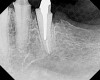

Figure 14  The preoperative radiograph showed an overhanging margin that was in close proximity to the bony crest.

Figure 14